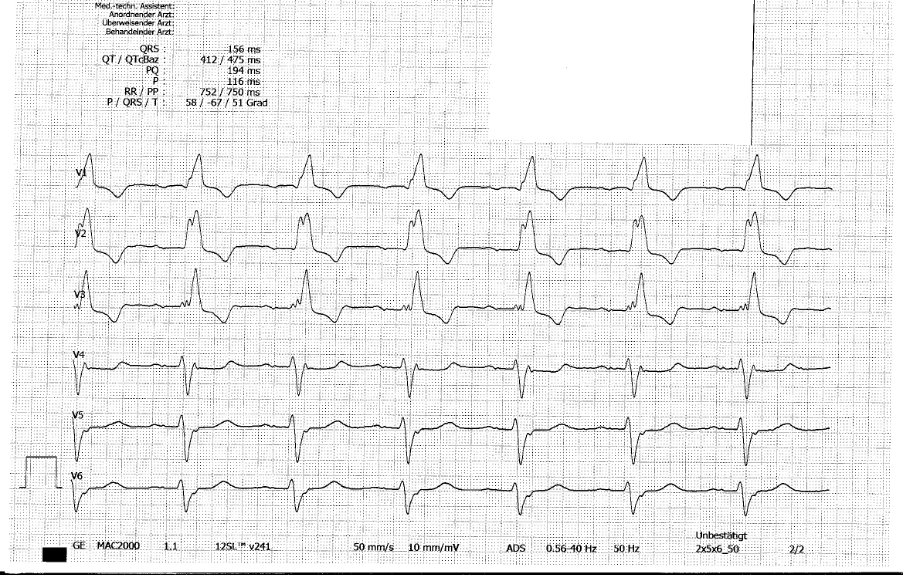

Große Begeisterung kannst du ihr allerdings nicht entlocken als du vor Therapie eine Basisdiagnostik empfiehlst. Sie möchte n a c h  H a u s e. Das 12-Kanal-EKG gehört bei dir natürlich trotzdem dazu. Du siehst folgendes:

Abb.1: Aufnahme-EKG Extremitäten- und Brustwandableitungen

Während diese Stimmen in deinem Kopf bleiben, liest du, was der Computer-Algorithmus des EKG als Diagnose auf das EKG gedruckt hat: „Normaler Sinusrhythmus. Linksachsen-Abweichung. Rechtsschenkelblock. Abnormale EKG.“

Zunächst gibst du die übliche Medikation (ASS und Heparin), klärst sie kurz über die notwendigen Maßnahmen auf und rufst beim diensthabenden Kardiologen an, um ihn darum zu bitten, das Herzkatheterlabor hochzufahren, denn…du weißt es besser als der Algorithmus: Hier liegt selbstverständlich nicht nur ein kompletter Rechtsschenkelblock vor, sondern es zeigen sich auch ST-Hebungen über der Vorderwand. Du weißt, dass in der Regel bei einem kompletten Rechtsschenkelblock bei den Ableitungen V1 bis V3 eine isoelektrische ST-Strecke oder gar ST-Senkungen auf der Gegenseite des Hauptvektors von QRS zu sehen sind („diskordante ST-Senkungen“). Wenn die ST-Strecke also nicht diskordant ist, ja nicht mal mehr isoelektrisch, sondern schon auf der gleichen Seite hebt („konkordante ST-Hebung“), muss ein akuter Koronarverschluss vorliegen. Wenn dann noch – wie in V3 – die T-Welle höher ist als der auf der gleichen Seite liegende QRS-Komplex, hast du noch einen Hinweis mehr auf eine akute Ischämie.

In Abb. 3 erkennst du nun einen „normalen“ kompletten Rechtsschenkelblock. ST ist in V1-V3 isoelektrisch bis leicht diskordant gesenkt. So darf es bei einem „normalen“ kompletten Rechtsschenkelblock aussehen.Zur Sicherheit legst du die beiden EKGs noch einmal nebeneinander und zeigst deinem Behandlungs-Team den Unterschied.